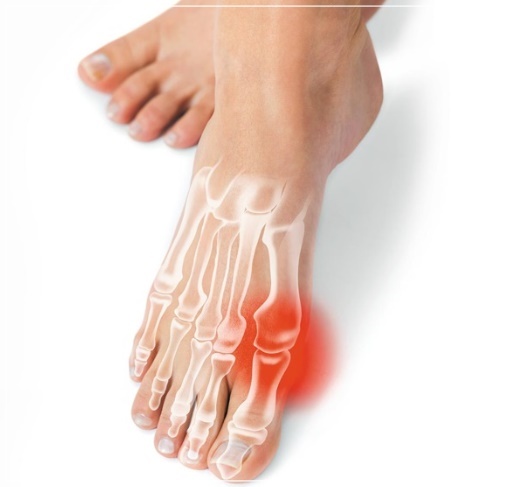

엄지 발가락의 튀어나온 관절부분(건막류)이 신발에 눌려 통증을 호소하는 것이 주 증상이나 엄지발가락이 둘째발가락 쪽으로 휘어져 있고, 관절이 안쪽으로 돌출되어 있습니다. 돌출된 관절은 서 있거나 걸을 때 자극을 받아 빨갛게 변하고 굳은살이 잡히며 염증과 통증이 발생합니다. 엄지발가락이 제 역할을 하지 못하니 발의 다른 부위에도 통증이 생기고 심해지면 발 모양의 변형, 허리의 통증 등이 발생합니다.

무지외반증 여부의 진단은 시진과 촉진(발가락 모양, 굳은살 등)으로 가능하지만 치료 방침을 결정하기 위해서는 방사선 검사가 필요합니다. 뼈와 뼈가 이루는 각도, 관절의 변형과 염증, 운동 범위 등을 측정합니다.